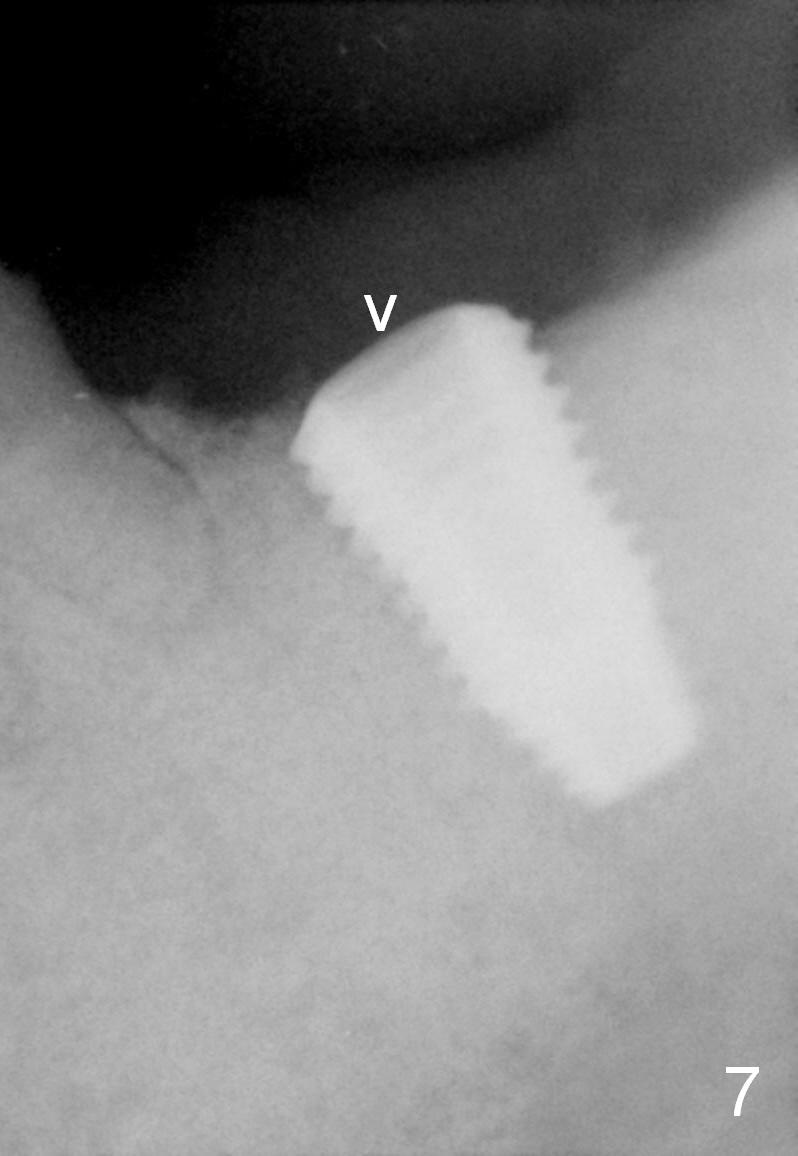

The patient returns 8 days postop, asymptomatic, but the wound is erythematous. Amoxicillin is refilled for extra one week. Two months postop, the incision heals (Fig.6); the healing screw is lost (Fig.7 arrowhead), while bone graft retains (Fig.8 *).